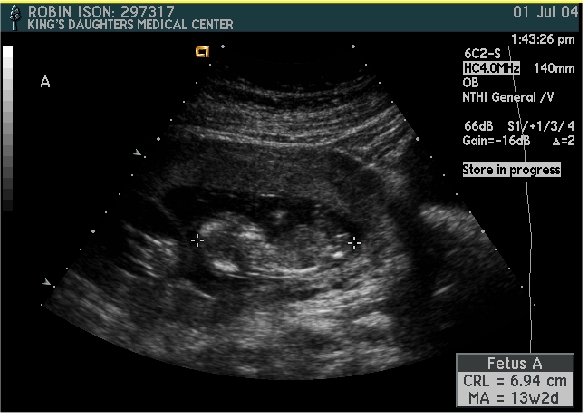

Baby A

Pictures from Ultrasound at 13 1/2 weeks.